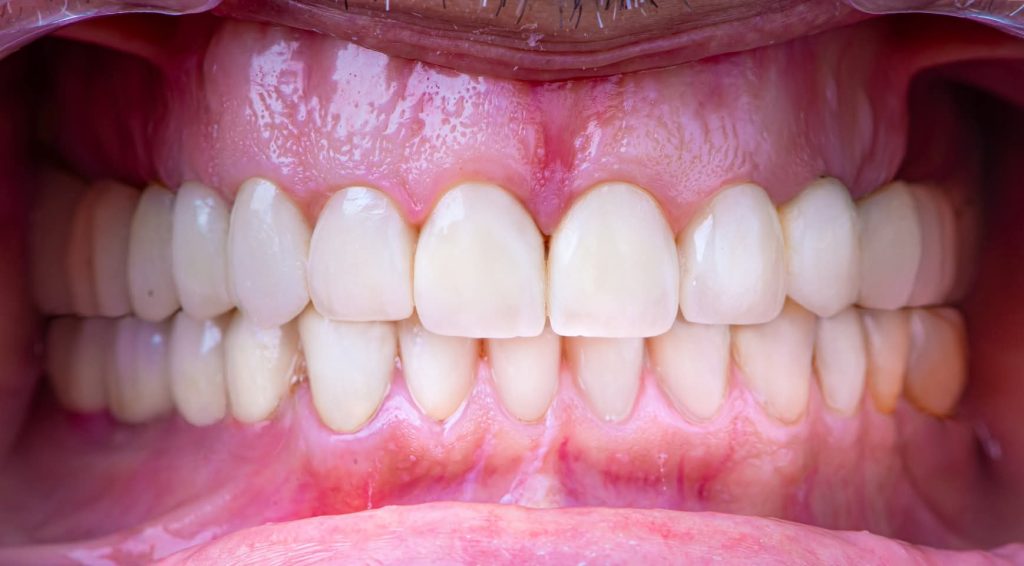

After almost 4 Years Follow-Up.

I am revisiting this Full Mouth Rehabilitation case, which was my first published case in this group.

3. Definitive Phase:

This phase began with the upper arch:

Placement of implants in the free-end areas.

Preparation of teeth and insertion of the fixed prosthesis.

The lower arch was managed similarly to the upper arch.

The patient has now been under follow-up for nearly 4 years and remains very happy and comfortable.